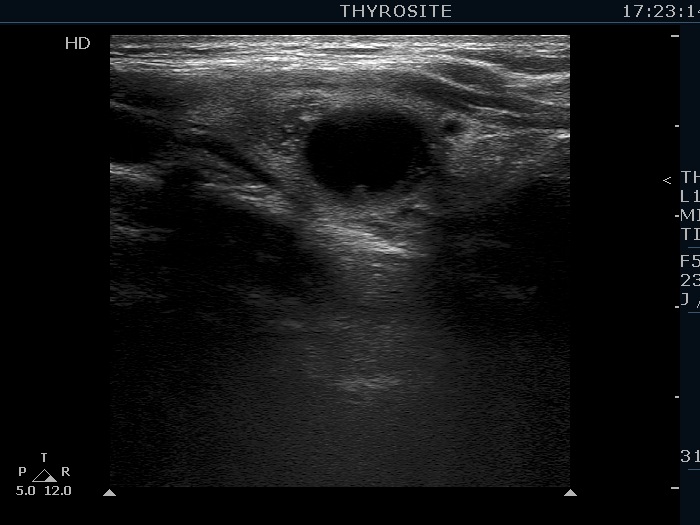

Ultrasonography. The thyroid was echonormal. There were several hypoechogenic lesions in the right lobe. The left lobe had an upper, solid and a lower cystic nodule. The former had both echonormal and moderately hypoechogenic parts and presented halo sign. The cystic nodule had a very tiny solid area in the dorsal part. Nonetheless, before aspiration it was unclear whether this would be a pure cyst or not. After aspirating 2 mL serous fluid a large, moderately hypoechogenic solid area replaced the previous cystic field and it became evident that this is in fact a central type cystic nodule.

Comment. This case illustrates why is it unsubstantiated to diagnose a pure cyst before aspiration. First, even the existence of a pure thyroid cystic nodule is debated if we use the term 'nodule' in pathological sense. Great proportion of smaller pure cystic lesions are in fact dilated macrofollicles covered with only few layers of follicular cells. Such cystic lesions completely disappear after the removal of the cystic content. But these lesions are not true nodules. Secondly, in most cases of true cystic nodules, which seem to be a pure cyst before aspiration, a solid area will appear after the removal of cystic content.